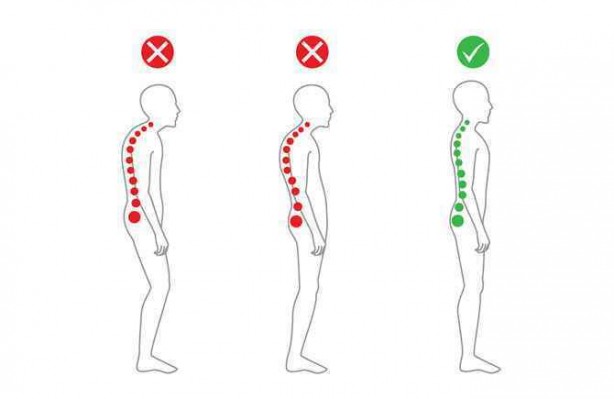

Duruş bozukluklarının fiziksel ve ruhsal olarak birçok soruna yol açabileceğini belirten Fiziksel Tıp ve Rehabilitasyon Uzmanı Dr. Esin Selimoğlu, yanlış duruş pozisyonlarının, boy kısalmasına dahi neden olabileceğini söyledi.